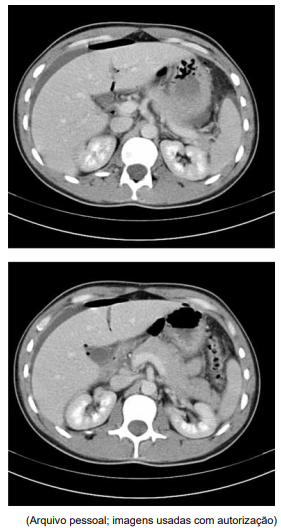

Ao exame físico, estava em regular estado geral e com fácies de dor, tendo apresentado vômito na admissão. A frequência cardíaca é de 125 bpm e a pressão arterial de 110 x 85 mmHg. Pouco colaborativo, não permite exame físico abdominal adequado por dor. Realizou o exame de imagem exibido a seguir e, após retornar do exame, evoluiu com rebaixamento do nível de consciência, hipotensão e má perfusão periférica.